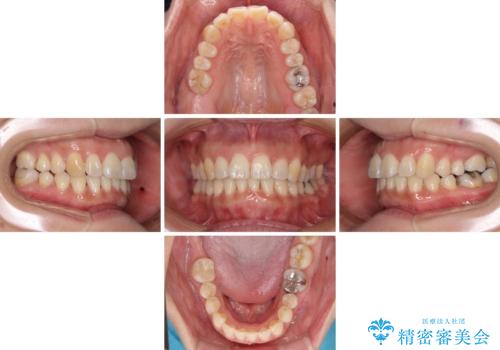

- 上下前歯の叢生を気にして来院された患者様です。

費用を抑え、期間もあまりかけずに治療をしたいとのことで、インビザライン・ライトを用いて矯正治療を行うこととしました。

インビザライン・ライトは、製作できるアライナーの枚数に制限があるため、移動可能な量に限りがあります。

一方で、半年から1年程度で治療を終えることができるため、軽度の歯列不正の患者様には大変お勧めです。